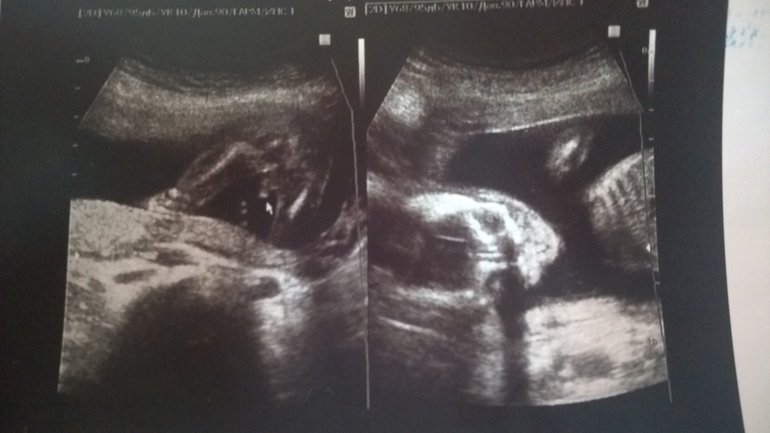

Результаты: УЗИ, КТГ, доплера, скринингаИ так, сегодня завершился еще один этап - мы прошли 2й скрининг. ттт все у нас хорошо, весиим уже 440 грамм. Ручкой маме на УЗИ махали, привет передавали))

А еще мы датчик узистки пытались оттолкнуть..не понравилось что - то. Вообще сына вялый был, спал наверное еще, да и не поварачивались личиком...кое как минут через 20 рассмотрели. ПДР так и не поменяли - 28 февраля.

Ну и наши фото)